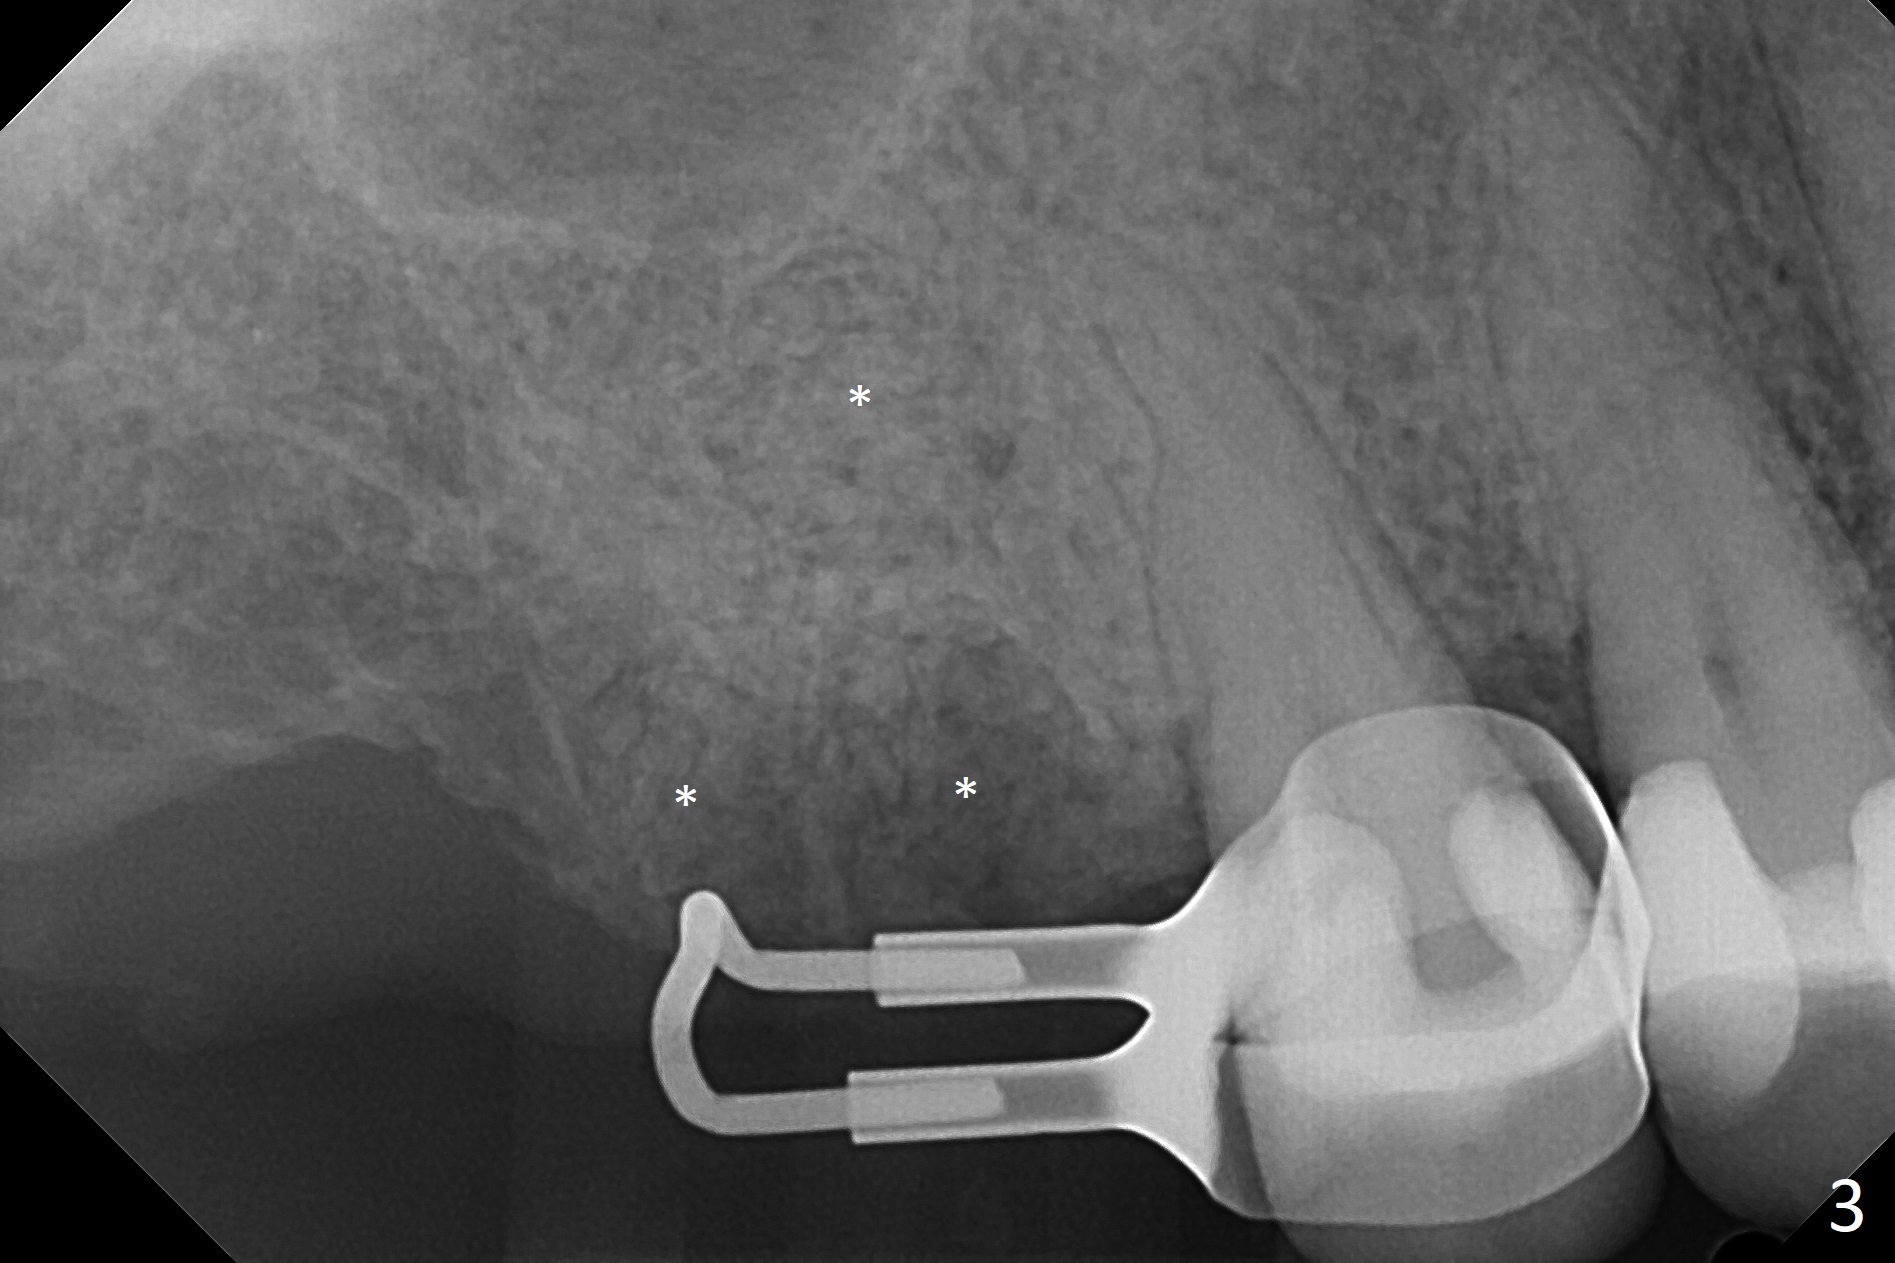

A 53-year-old woman wants to extract the tooth #3 with recurrent apical periodontitis (Fig.1). Socket preservation is conducted (Fig.2). The tooth is terminal in the arch and difficult to keep periodontal or acrylic dressing in place. To overcome the situation, a prefabricated space maintenance is placed without cementation because of its inherent fitness (Fig.3). Periodontal dressing (Fig.4 D) appears to be retained in place. The spacer is lost prematurely due to no cement, but the wound appears to be healing 13 days postop (Fig.5,6). The socket heals 3 months postop (Fig.7,8). However the ridge is narrow 19 months postop (Fig.9, as compared to that of the tooth #14 (Fig.10)).